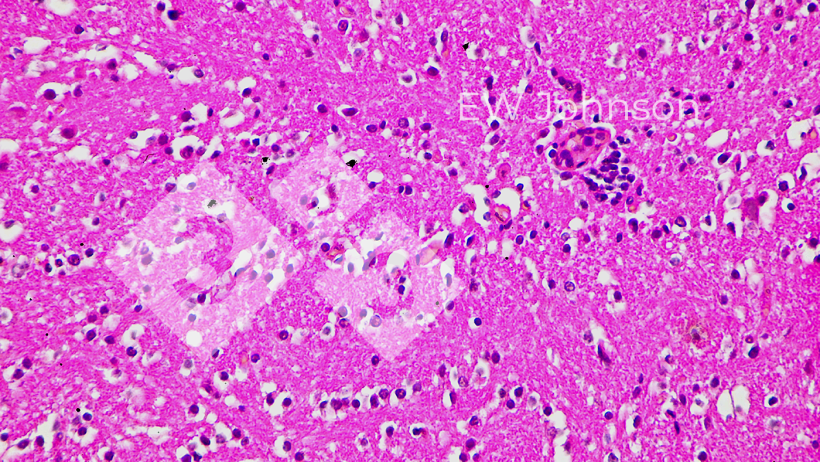

A PCR foi negativa para PRRS, pseudo-raiva (doença de Aujeszky), circovírus suíno PCV2 e PCV3, peste suína clássica (PSC) e peste suína africana (PSA). A granja era conhecida como livre de PRRS, Aujeszky, Circovirose e PSA antes deste evento. A PCR para Getahvirus em pulmão de leitão foi altamente positiva. A histopatologia revelou pneumonia intersticial grave (Figura 3) e meningoencefalite fibrino-hemorrágica (Figura 4). Foi diagnosticada doença perinatal por Getahvirus. A granja foi informada de que esta doença é transmitida principalmente por mosquitos e medidas de controle foram aplicadas. Não houve mais casos ou sinais clínicos na granja e a produção voltou ao normal.